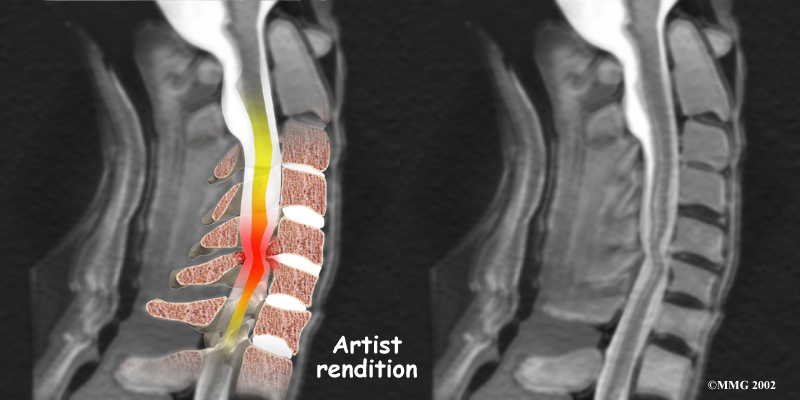

The nucleus may push through the weakened and torn annulus and into the spinal canal. This is called a herniated or ruptured disc. The disc material that squeezes out can press against the spinal nerves. The disc also emits enzymes and chemicals that produce inflammation. The combination of pressure on the nerves and inflammation caused by the chemicals released from the disc cause pain.

- Herniated Disc: Heavy, repetitive bending, twisting, and lifting can place extra pressure on the shock-absorbing nucleus of the disc. If great enough, this increased pressure can injure the annulus (the tough, outer ring of the disc). If the annulus ruptures or tears, the material in the nucleus can squeeze out of the disc. This is called a herniation. Although daily activities may cause the nucleus to press against the annulus, the body is normally able to withstand these pressures. However, as the annulus ages, it tends to crack and tear. It is repaired with scar tissue. Over time, the annulus becomes weakened, and the disc can more easily herniate through the damaged annulus.

If the herniated disc material presses against a nerve root it can cause pain, numbness, and weakness in the area the nerve supplies. This condition is called cervical radiculopathy (mentioned earlier). And any time the herniated nucleus contacts tissues outside the damaged annulus, it releases chemicals that cause inflammation and pain. If the nucleus herniates completely through the annulus, it may squeeze against the spinal cord. This causes a condition that is even more serious because it affects all the nerves of the spinal cord. This condition is called cervical myelopathy.

Cervical Myelopathy